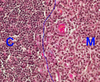

What tissue is this?

bone marrow

left of the yellow line

cortex (thymus)

right of the yellow line

medulla (thymus)

Trabeculae (of thymus)